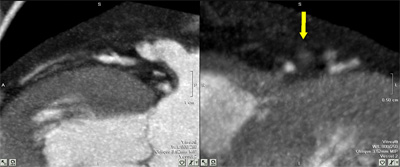

Ventriculograma izquierdo por TC multicorte. Cavidad ventricular en reloj de arena, aneurisma apical de cuello angosto. El diagnóstico diferencial con el pseudoaneurisma ventricular es dificultoso.